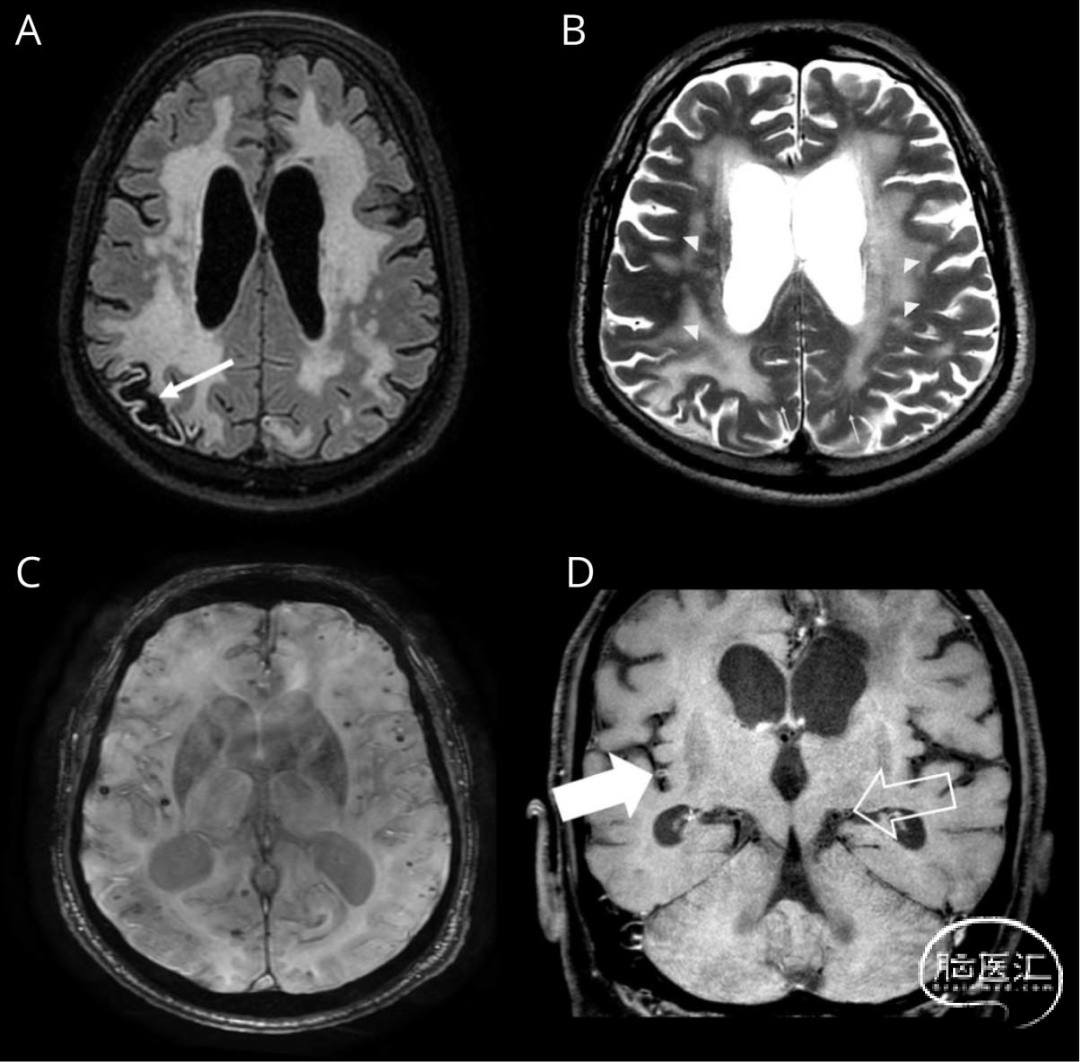

图1 脑部MRI表现。轴位T2/FLAIR序列(A)与T2/TSE序列(B)显示:右顶叶陈旧性缺血病灶(A图箭头),广泛融合性脑白质病变(A图),病变区域周边血管周围间隙扩大(B图细箭头),受累区域边界清晰(B图箭头标示)。轴位SWI序列(C)可见:多发脑叶表浅微出血(基底节及丘脑未受累),右额叶皮质表面铁沉积证据。冠状位血管壁成像(D)显示:左大脑后动脉P3段(空心箭头),右大脑中动脉M2段(实心箭头),呈同心性血管壁对比强化: